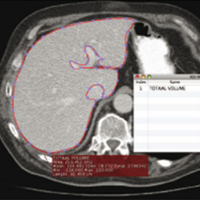

Virtual liver resection and volumetric analysis of the future liver remnant using open source image processing software (2010)

van der Vorst, Joost R and van Dam, Ronald M and van Stiphout, Rogier SA and van den Broek, Maartje A and Hollander, Ilona H and Kessels, Alfons GH and Dejong, Cornelis HC

World journal of surgery, vol. 34 (10): 2426–2433